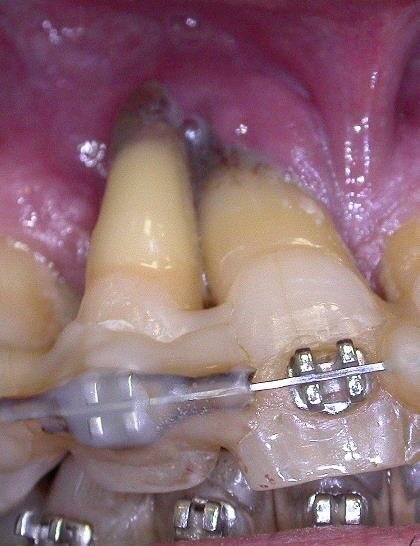

Iniziano le terapie (ablazioni tartaro, ortodonzia, scaling e root planing, curettages gengivali, farmaci nelle tasche, laser, test microbiologici ripetuti e trattamenti endocanalari) che si protraggono da febbraio 2012 al maggio 2015. Costo? Circa 11.500 euro, ma inizialmente i risultati ci sono: il paziente sta meglio, l’alitosi si ridimensiona, i denti perdono l’iniziale mobilità e si sono rapidamente allineati, anche se il livello di igiene domiciliare non è proprio migliorato.

Poi, però, la situazione cambia: i denti si sventagliano, alcuni risultano avulsi dagli alveoli (12, 22, 15, 25) restano in bocca solo perché attaccati al filo ortodontico. Altri si muovono più di prima. Poi qualche dente viene spontaneamente “sputato”. Il dottore da la colpa alla scarsa igiene domiciliare e propone alcune estrazioni (12, 22, 15, 25), interventi di chirurgia parodontale, altra endodonzia e protesi, con ulteriore richiesta di € 15 mila euro.

Alla visita del CTU le condizioni cliniche sono peggiori di quelle oggettivate (Figg. 1-4) alla fine del rapporto. Il riconoscimento di concorrenza di cause porta ad accollare a YZ solo parte dei danni rilevati (danno biologico 1% e ITP al 10% per 50 giorni), ma l’inadempimento fa riconoscere anche l’obbligo di rendere quanto percepito per prestazioni inutili e non indicate. Dovrà quindi restituire di tasca propria competenze per almeno 10.000 euro oltre alla franchigia prevista dal contratto di polizza in materia di risarcimento e alle spese legali. Nelle incaute promesse il Giudice riconosce, inoltre, un grosso vizio di consenso.